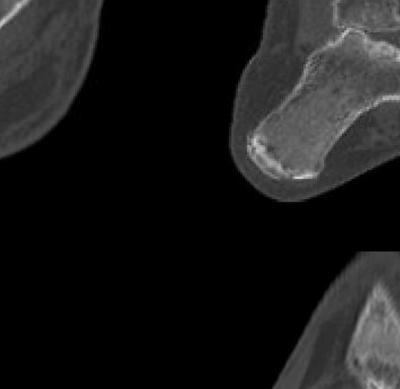

921 Charcot Neuroarthropathy of the Foot and Ankle in the Acute Setting: An Illustrative Case Report and Targeted Review

Kian Bagheri, Albert T. Anastasio, Alexandra Krez, Lauren Siewny, Samuel B. Adams